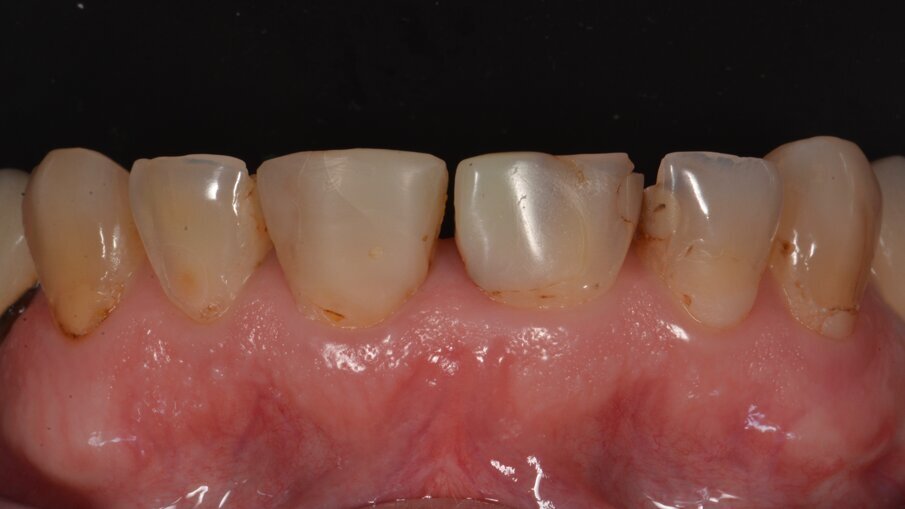

De beginsituatie: we zien sterk versleten centrale snijtanden met verkeerde lengte-breedte-proporties met veel verschillende tand-tinten.

Vooraanzicht van het bovenfront: veel oude vullingen zijn aan vervanging toe door slechte randaanpassing en/of verkeerde kleuren.